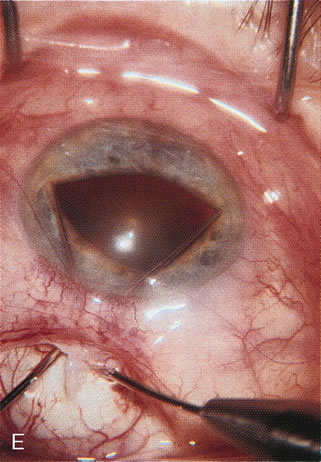

A patient with long-standing primary open-angle glaucoma with a successful glaucoma filtration procedure and IOP of 10 mm Hg on no antiglaucoma medications develops a significant, moderately dense nuclear sclerotic cataract. This patient is best served by small incision cataract extraction with foldable IOL implantation. Less desirable options include ECCE with IOL implant via clear cornea, temporal limbus, or inferior approach. Astigmatism, wound instability, prolonged visual recovery, visual fluctuation, exposed sutures, and bleb failure are the major drawbacks to large-incision lens extraction. Even after the surgeon has mastered large-incision clear corneal cataract extraction, long-term wound shift and astigmatism are a chronic problem (Fig. 6). Inferior cataract extraction is difficult for those not experienced with it. With the advent of small-incision phacoemulsification surgery, the surgeon is now able to use a limbus approach adjacent to the bleb or a clear corneal temporal approach. Postoperative inflammation is less with the smaller incision, and filtering blebs are more likely to survive. Patients with IOP greater than 10 mm Hg after a filtering procedure are more likely to experience permanent IOP elevation after phacoemulsification. Patients should understand that IOP elevation post cataract extraction is always an issue, even with a functioning filter.

Fig. 6. ECCE following trabeculectomy. The larger corneal incision associated with ECCE leads to a host of problems that are typically less severe with small incision cataract surgery. With improved phacoemulsification techniques, this type of incision is infrequently encountered. This bleb failed following ECCE, and topical antiglaucoma therapy was restarted. Long-term wound drift; astigmatism, and corneal decompensation are additional visual factors. However, when the nucleus is brunescent and phacoemulsification risky, surgeons with the skill to convert to ECCE through a clear corneal incision are at a significant advantage. This 11-mm free hand incision takes considerable practice and skill to master.